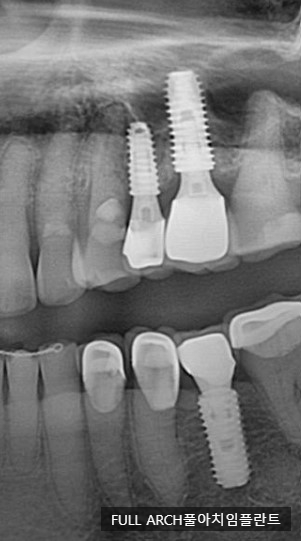

오늘 다녀가신 환자의 임플란트 엑스레이 입니다. 아래 나선형으로 보이는 게 픽스쳐 이며 크라운과 연결해 주는 어버트 먼트와 크라운 이렇게 세가지 구조물로 되어 있습니다.

티타늄으로 되어 있으며 치아의 뿌리를 담당하고 있는 중요한 구조물이라고 할 수 있습니다.

뼈에 식립하며 이는 나선형으로 되어 있습니다.

뼈와 결합하는 과정에서 중요한 수술이 되기도 하며, 뼈가 많은 경우 더 쉽고 단단하게 붙을 수 있습니다.

중간기둥이라고 편하게 말할 수 있는데 픽스쳐와 보철물을 연결해주는 역할을 하고 있습니다.

우리가 흔하게 말하는 크라운 인데 음식을 씹기도 하는 기능과 심미적인 역할을 하게 됩니다.

지르코니아라는 재료나 PFM이라는 재료를 주로 사용하며 보철물은 기성품이 아닌 환자구강구조에 맞춰 커스텀으로 만들어집니다.